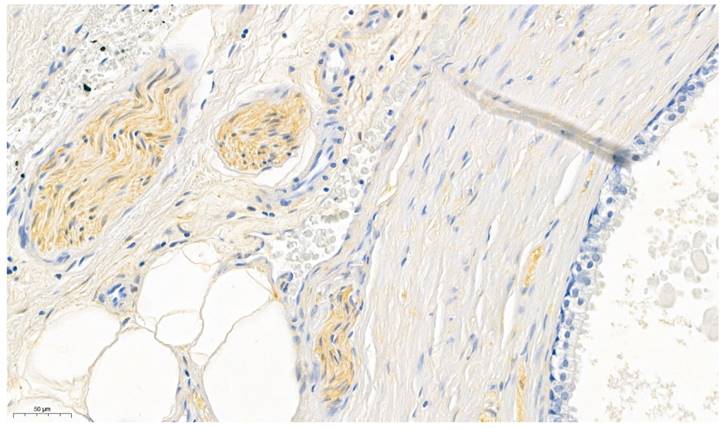

As positive control peripheral nerve bundles (in prostate specimen), known for its consistent expression of ALDH1A1 (31), were used (Figure 1). The surrounding prostatic glands served as internal negative control (32). Furthermore omission of the primary antibody was conducted for negative control.

Figure 1

Prostate specimens were used for validating the ALDH1A1 antibody. The perinueral sheaths served as positive controls whereas the prostatic glands served as internal negative controls.